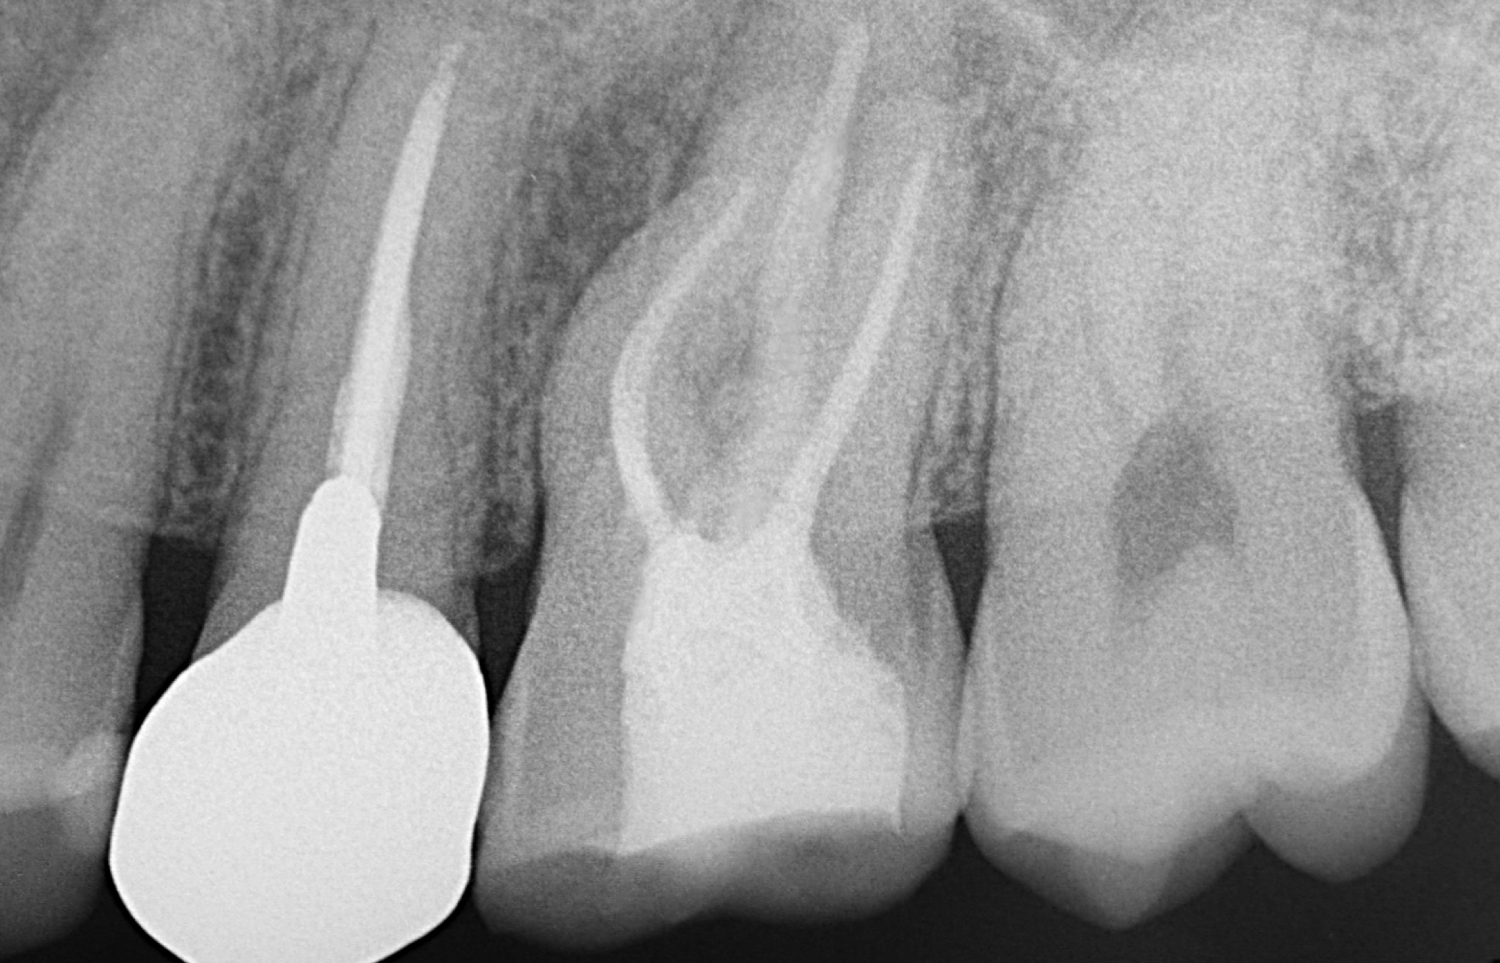

正放線投影(正面からまっすぐ)

根管治療の症例

偏遠心投影(後ろ(奥側)からナナメに)

2週間ほどズキズキした痛みが続き、温かいものがしみる症状がありました。かかりつけでは「抜髄が必要かもしれない」として紹介となりましたが、歯内療法の専門的な検査で感染や根の病気の可能性を丁寧に確認したところ、抜髄を急ぐ所見が乏しい状態でした。いったん経過観察とし、1週間後に痛みが消失。再評価でも所見は変わらなかったため、抜髄は行わず、修復物の調整・やり替え対応で終了しました。

年齢性別 40代・女性

主訴 2週間前からズキズキ痛む/温かいものがしみる

治療部位 左上7番

治療内容 診査・診断 → 経過観察 → 再評価 → 抜髄は行わず、修復物のやり替え依頼

治療回数 検査回数2回

リスク副作用 検査や経過観察の間に症状が再燃する可能性があります。必要に応じて追加検査や治療方針の変更が必要になる場合があります。